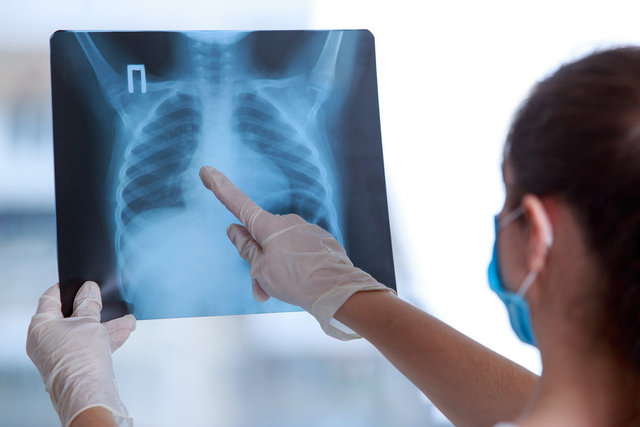

TANI KONULDUĞUNDA ÇOK GEÇ OLABİLİR

Akciğer kanserinin genellikle ileri evrede belirti verdiğini söyleyen Prof. Dr. Görgüner, "En belirgin belirtisi karakter değiştiren öksürüktür. Bunu nefes darlığı, göğüs ağrısı ve kanlı balgam takip eder. İleri evrelerde ses kısıklığı, boyunda ve yüzde şişlik, omuz ağrısı, kolda güçsüzlük, yaygın vücut ağrıları görülebilir. Horner sendromu olarak adlandırılan göz kapağında düşme, göz bebeğinde küçülme ve aynı tarafta yüzün yarısında terleme bozukluğu belirtiler arasındadır. Tanısı konmuş hastaların yüzde 30´unda akciğerde su toplaması meydana gelmektedir. Ayrıca iştahsızlık, kilo kaybı, yorgunluk gibi diğer birçok kanser türünde görülebilen belirtiler de akciğer kanserinde yer alabilir.

Bu belirtilerden herhangi birinin yaşanması durumunda mutlaka bir göğüs hastalıkları bölümüne başvurulmalıdır. Çünkü akciğer kanseri sinsi bir hastalıktır ve genellikle geç belirti verir. Bu durum hastalığın erken tespit edilme olasılığını azaltır ve dolayısıyla tedavi şansını düşürür. Bu nedenle belirli risk faktörlerine sahip kişiler mutlaka düzenli tıbbi kontrollerini yaptırmalı ve belirtileri ciddiye almalıdır" dedi.